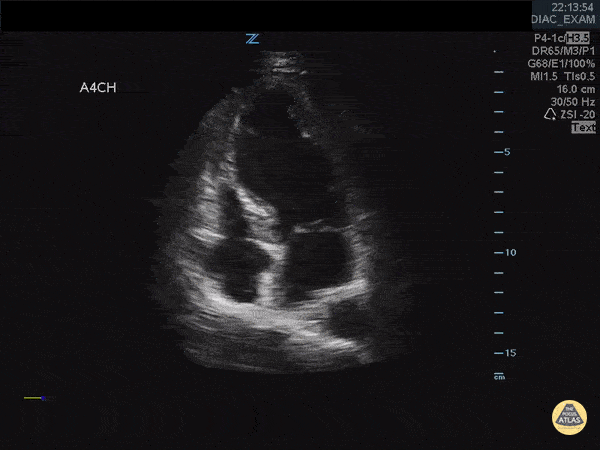

Left Ventricular Dysfunction - Takotsubo Cardiomyopathy in a Patient with Chest Pain

The Case: A 45 year old with history of diabetes presented with chest pain and shortness of breath. Cardiac #POCUS demonstrates LV apical ballooning with basal hypercontraction consistent with Takotsubo. This was confirmed with normal coronaries on cardiac cath. Image courtesy of IUEM Ultrasound Original Twitter Post can be found here.